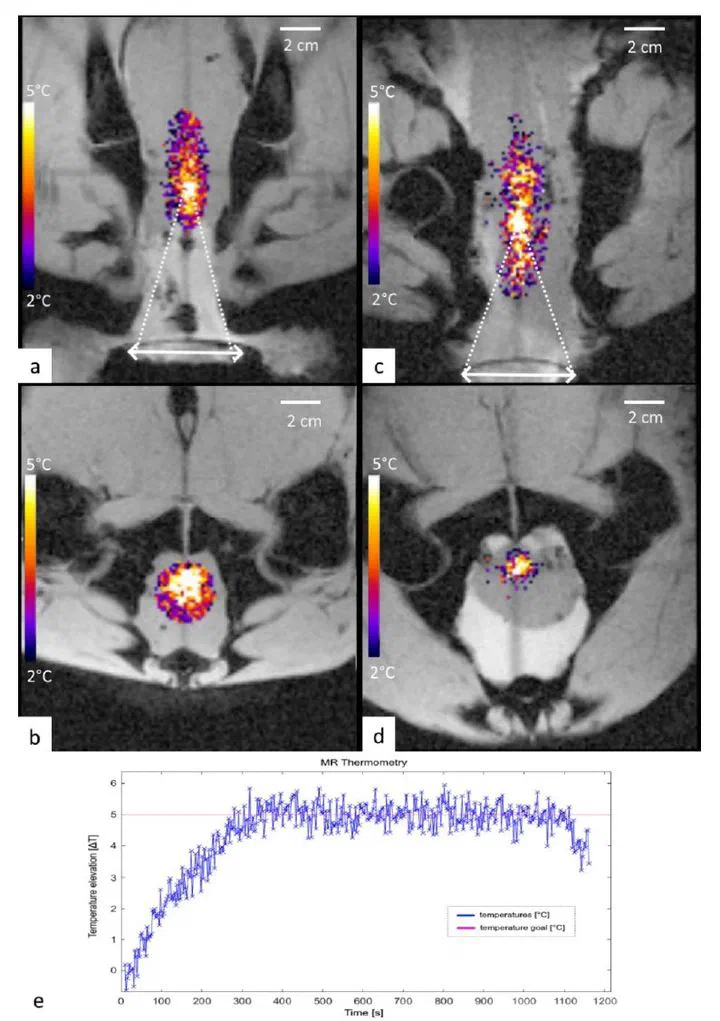

Image of MRI thermometry showing focal heating MRI thermometry

Design, embodiment, and experimental study of a novel concept of extracorporeal phased array ultrasound transducer for prostate cancer regional deep hyperthermia treatments using a transperineal acoustic window is presented. An optimized design of hyperthermia applicator was derived from a modelling software where acoustic and thermal fields were computed based on anatomical data. Performance tests have been experimentally conducted on gel phantoms and ex vivo tissues, under 3T MRI guidance using PRFS thermometry. Feedback controlled hyperthermia (ΔT=5°C during 20 min) was performed on two ex vivo lamb carcasses with prostate mimicking pelvic tissue, to demonstrate capability of spatio-temporal temperature control and to assess potential risks and side effects. Our optimization approach yielded a therapeutic ultrasound transducer consisting of 192 elements of variable shape and surface, pseudo randomly distributed on 6 columns, using a frequency of 700 kHz. Radius of curvature was 140 mm and active water circulation was included for cooling. The measured focusing capabilities covered a volume of 24×50×60 mm3. Acoustic coupling of excellent quality was achieved. No interference was detected between sonication and MR acquisitions. On ex vivo experiments the target temperature elevation of 5°C was reached after 5 min and maintained during another 20 min with the predictive temperature controller showing 0.2°C accuracy. No significant temperature rise was observed on skin and bonny structures. Reported results represent a promising step toward the implementation of transperineal ultrasound hyperthermia in a pilot study of reirradiation in patients with prostate cancer.